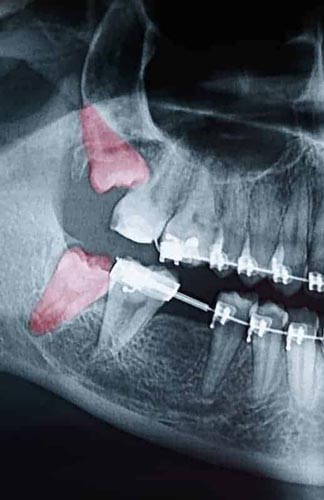

Though some patients may not require the removal of their wisdom teeth, most often, it’s needed to protect your overall oral health. Wisdom teeth can begin to grow in sideways, only partially erupt, or even get stuck beneath the gum and bone. Known as impacted teeth, those that get stuck may resort to shifting position as the try to find a pathway for eruption. When wisdom teeth don’t erupt through the gumline properly, they can create severe problems for the patient, including:

- Risk of infection in tissues surrounding the tooth

- Disruption to the orthodontic or natural alignment of teeth

- Formation of tumors or cysts around impacted wisdom teeth, resulting in jawbone or tooth destruction.

To evaluate the state of your wisdom teeth, we’ll first do a thorough examination and take x-rays of your mouth. This will help us determine if your wisdom teeth pose a current or future threat to your oral health. Early detection of issues results in better outcomes for our patients, so we recommend the first evaluation be completed in a patient’s mid-teenage years.